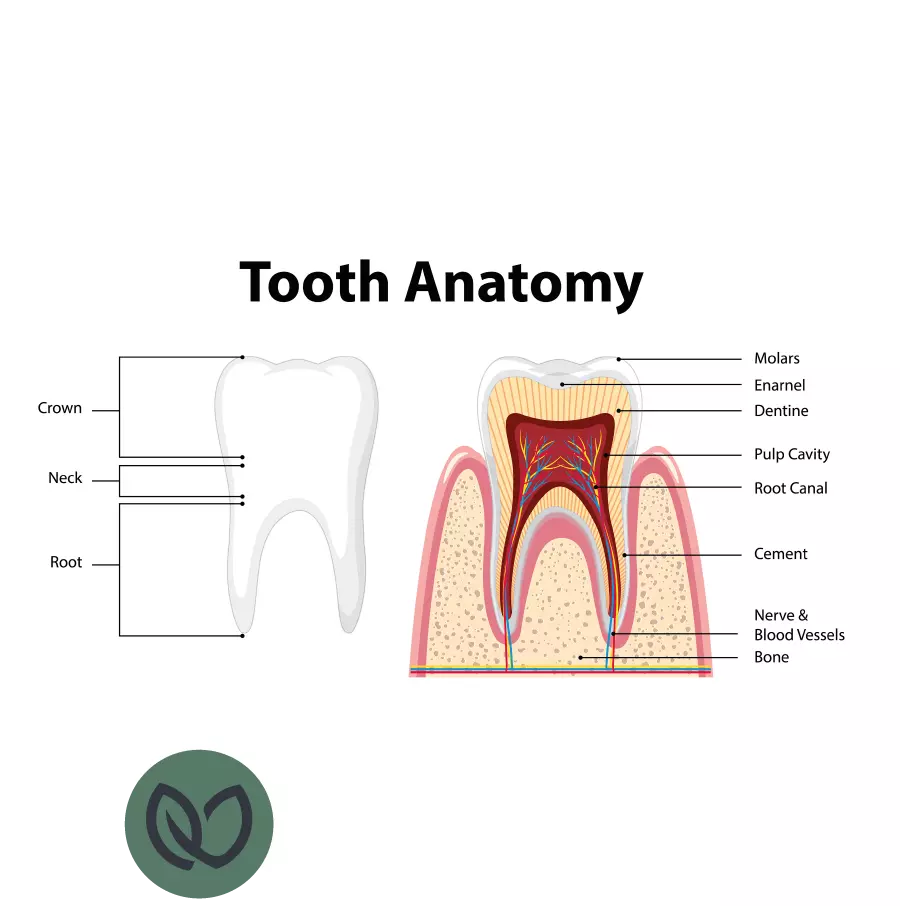

Cariës is een progressieve aandoening waarbij het glazuur van de tanden wordt aangetast door zuren geproduceerd door bacteriën in je mond. Het begint meestal met kleine, onzichtbare plekjes op het glazuuroppervlak, maar kan zich geleidelijk uitbreiden naar dieper gelegen weefsels, zoals het dentine.

Glazuurcariës begint op het buitenste beschermende laagje van je tanden, het glazuur. Deze vorm van cariës hoeft niet altijd behandeld te worden, aangezien het glazuur zichzelf kan herstellen door een goede mondhygiëne en het fluorideren van de tanden. Dentinecariës treedt op wanneer het cariësproces zich verder ontwikkelt en het onderliggende dentine aantast, dat gevoeliger is en kan leiden tot pijn en gevoeligheid. Deze vorm van cariës moet echter wel behandeld worden.

De behandeling van cariës kan variëren afhankelijk van de ernst van de aandoening. In het algemeen omvat de behandeling het verwijderen van het aangetaste tandweefsel en het vullen van het gat met tandvullingen. In gevorderde gevallen kan een wortelkanaalbehandeling of extractie van de tand noodzakelijk zijn.